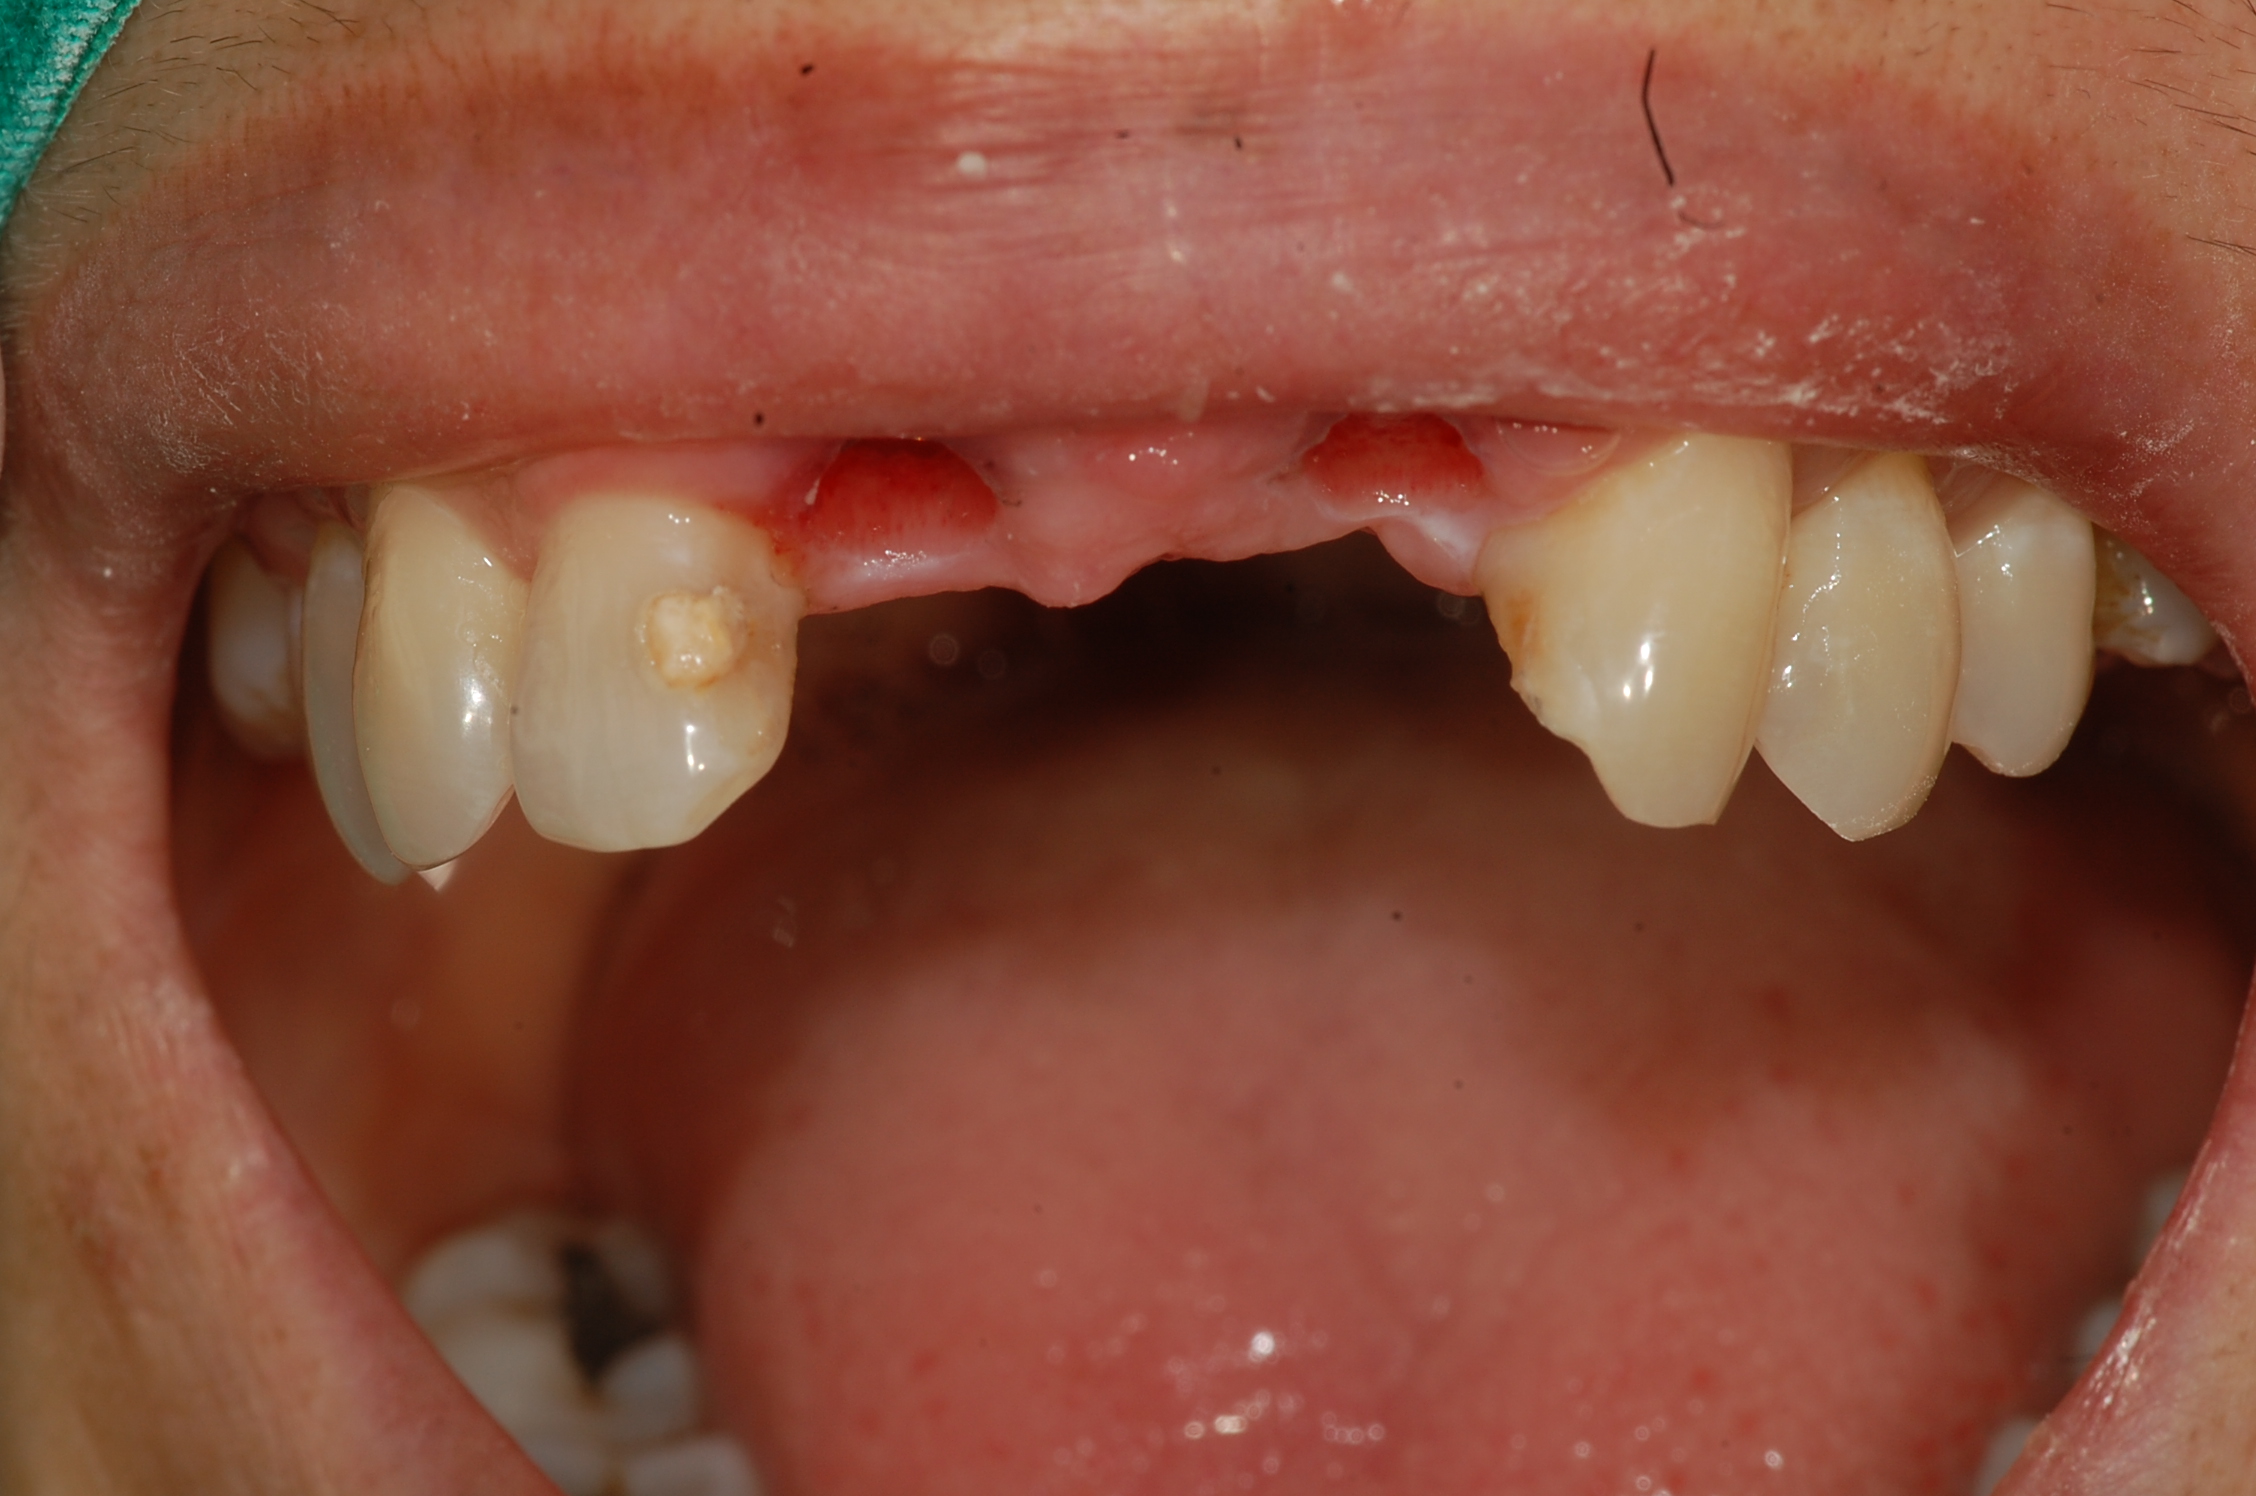

[임플란트] 제목 : 전치부 임플란트 브릿지

앞니의 임플란트입니다.